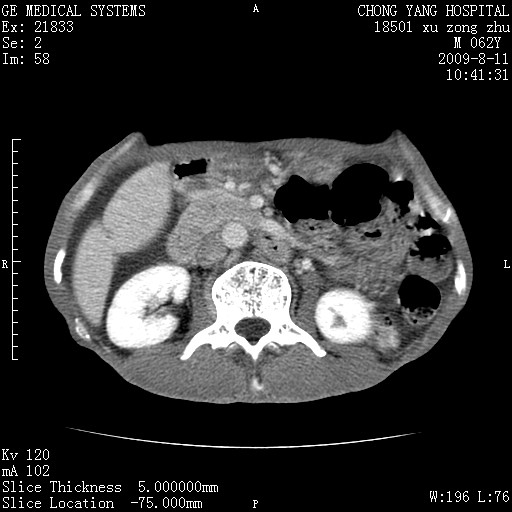

以下是引用杀毒软件在2009-8-11 16:35:00的发言:[br]肝内胆管扩张局限于左叶,胆管内有结石伴肝外胆管结石,胆管壁增厚呈弥漫性并发腹腔积液,胰腺边界模糊。[br][br]考虑---胆总管及肝内胆管结石继发胆管炎及胰腺炎,左肾下极囊肿,腹水。

以下是引用zjzjr在2009-8-11 17:35:00的发言:[br]肝内胆管扩张局限于左叶,胆管内有结石伴肝外胆管结石,胆管壁增厚呈弥漫性并发腹腔积液。[br][br]考虑---胆总管及肝内胆管结石继发胆管炎,左肾下极囊肿,腹水。